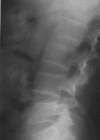

Case presentation: We describe two cases of non-traumatic acetabular and vertebrae fractures following seizures without history of epilepsy. They occurred in two male patients, 18 and 48 years old suffering respectively from hypercorticism and poorly controlled diabetes mellitus. Seizures, occurring inside hospital, were secondary to hypertensive encephalopathy crisis with hypokaliemia in the first case and severe hypoglycaemia in the second one. Fracture was promoted by a decrease in mineral bone density caused respectively by hypercorticism and diabetic chronic renal failure.